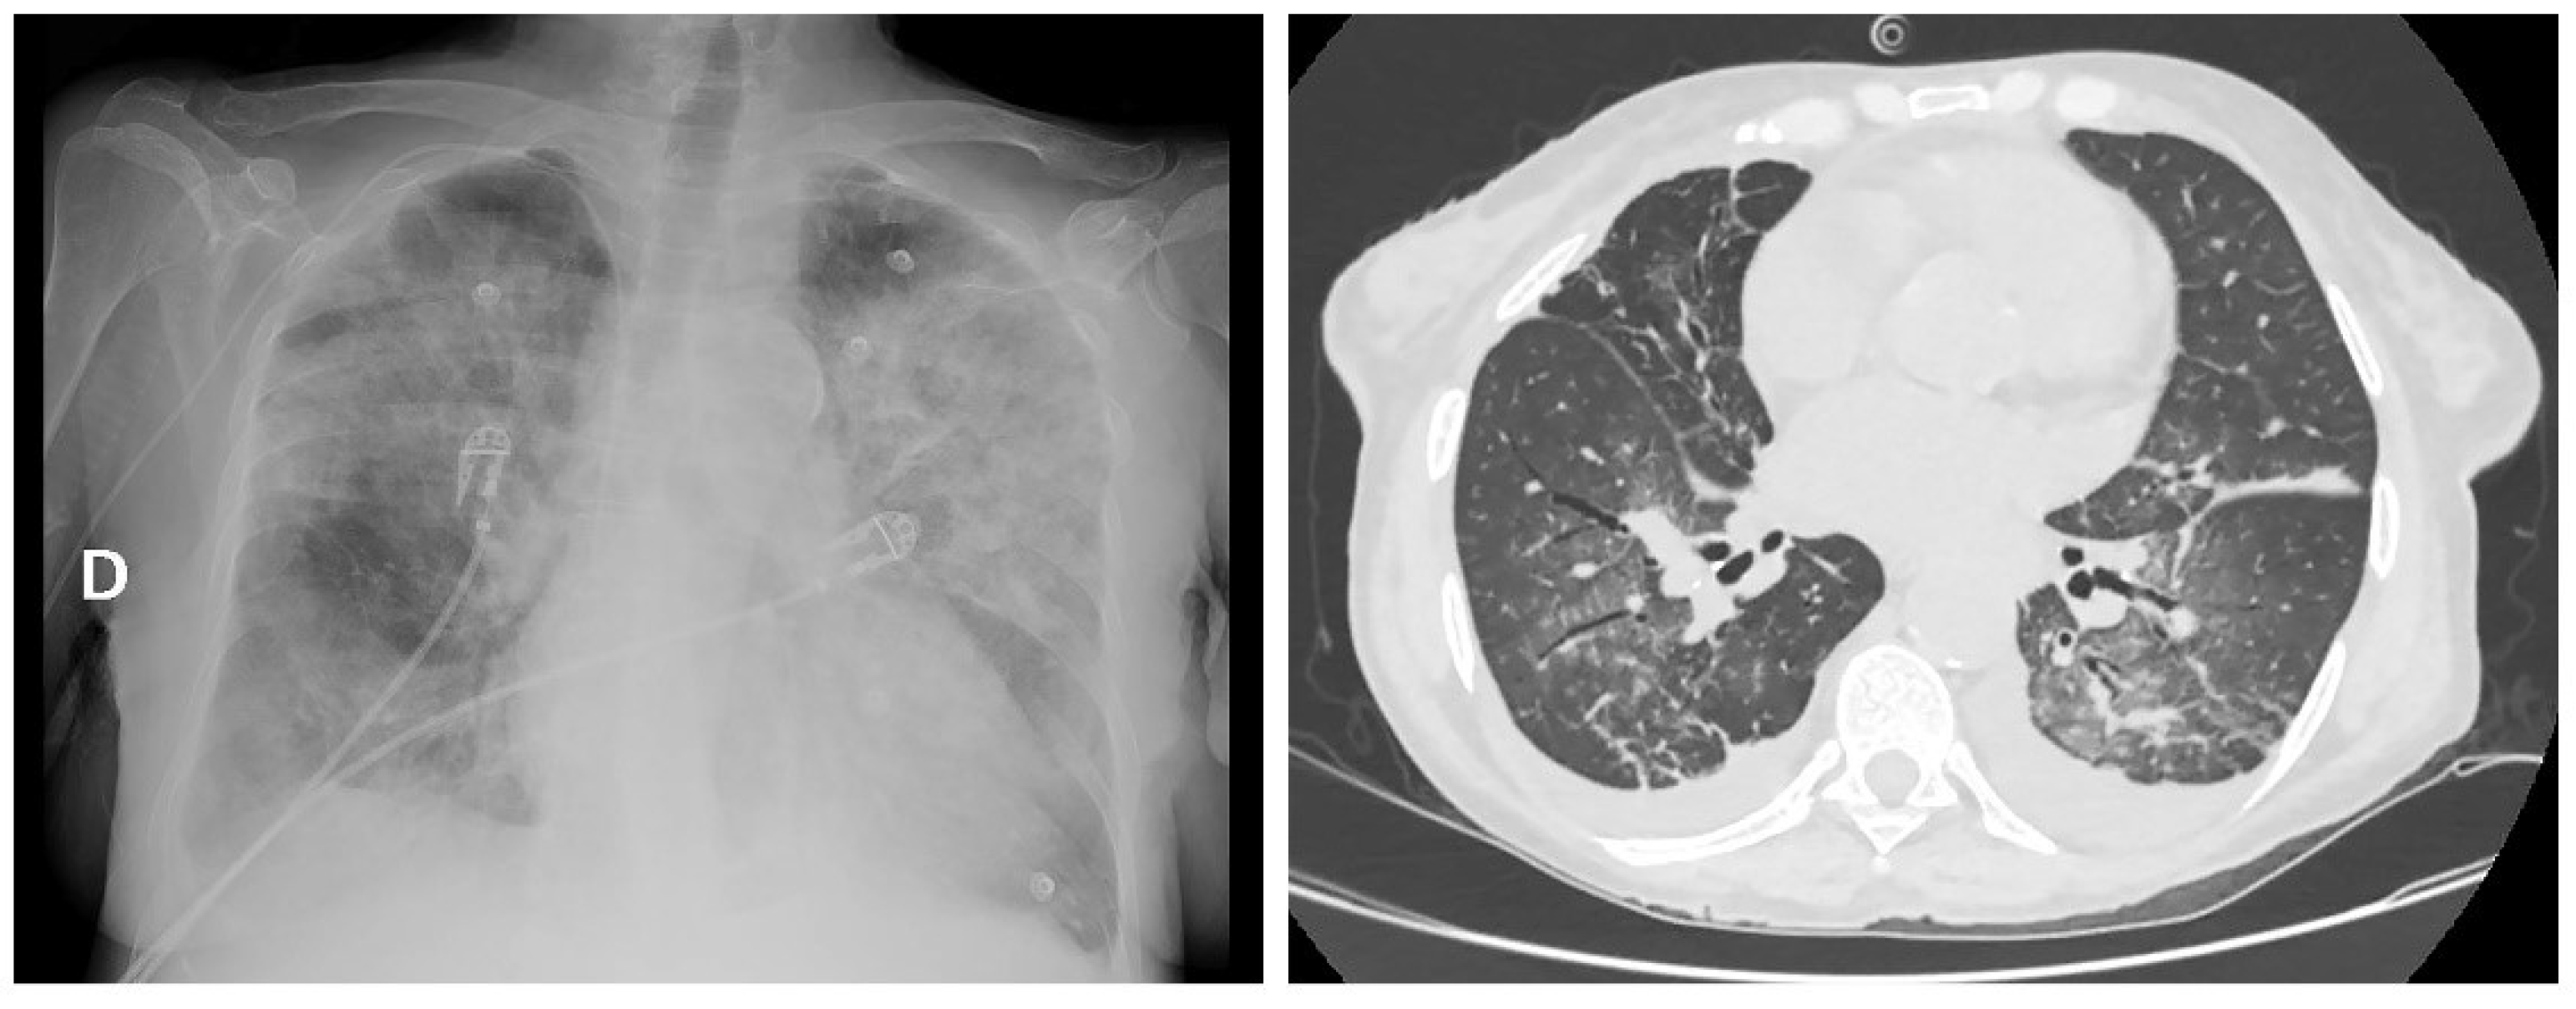

2. Case Report